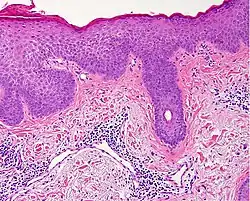

| ||

| Lichen planus | Irregular epidermal hyperplasia with a jagged “sawtooth” appearance, compact hyperkeratosis or orthokeratosis, foci of wedge-shaped hypergranulosis, basilar vacuolar degeneration, slight spongiosis in the spinous layer, and squamatization. The dermal papillae between the elongated rete ridges are frequently dome shaped. Necrotic keratinocytes can be observed in the basal layer of the epidermis and at the dermal-epidermal junction. Eosinophilic remnants of anucleate apoptotic basal cells may also be found in the dermis and are referred to as “colloid or civatte bodies”. Whickham striae are usually seen in the areas of hypergranulosis. Vacuolar degeneration at the basal layer may be noted leading to focal subepidermal clefts (Max Joseph spaces). Squamatization occurs as a result of maturation and flattening of cells in the basal layer. It happens in areas of marked hypergranulosis with prominence of the sawtooth pattern of rete ridges. Wedge-shaped hypergranulosis can occur in the eccrine ducts (acrosyringia) or hair follicles (acrotrichia). In the hypertrophic subtype, the associated hyperkeratosis, parakeratosis, hypergranulosis, papillomatosis, acanthosis, and hyperplasia markedly increased with thicker collagen bundles forming in the dermis. Moreover, the rete ridges are more elongated and rounded as opposed to the typical sawtooth pattern. In atrophic LP, loss of the rete ridges and dermal fibrosis is prominent. In vesiculobullous LP, the disease progression is quicker. Hence, some of the distinctive features such as hyperkeratosis, hypergranulosis, or dense lymphocytic dermal-epidermal infiltrate may not be present. LP lesion may resolve with residual hyperpigmentation caused by a persistent increase in the number of melanophages in the papillary dermis.[9] |  |   |